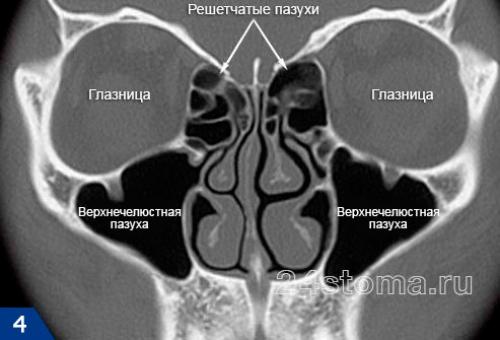

Синусит (от лат. sinusitis) – это воспаление слизистой оболочки, которая выстилает изнутри придаточные пазухи носа. Воспаление может локализоваться только в одной из пазух, либо сразу в нескольких. Чаще всего воспалению подвержены верхнечелюстные синусы (гайморовы пазухи), которые расположены в проекции верхушек корней 5-6-7 зубов с каждой стороны верхней челюсти. Такое заболевание принято называть терминами – верхнечелюстной синусит или гайморит (рис.2).

Синусит (помимо верхнечелюстных пазух) может также локализоваться в лобных пазухах, клиновидных пазухах, а также в ячейках решетчатой кости. Для его обозначения в этих случаях используются термины – фронтит, сфеноидит и этмоидит, соответственно. Однако, чаще всего пациентам приходится сталкиваться именно с верхнечелюстным синуситом, что связано прежде всего с некоторыми анатомическими особенностями верхнечелюстных пазух.

Что представляют из себя верхнечелюстные пазухи –

Таких пазух две (по одной с каждой стороны верхней челюсти). Средний размер верхнечелюстных пазух у взрослого: от 2,5 до 3,5 см – в ширину, от 3,6 до 4,5 см – в высоту, от 3,8 до 4,5 см – в глубину. Заполнены пазухи воздухом, а внутренняя их поверхность выстлана слизистой оболочкой. На рис.3 вы можете увидеть, что верхняя костная стенка пазухи является одновременно нижней стенкой глазницы, а дно каждой пазухи – отделено от верхушек корней 5-6-7 зубов лишь тонким слоем костной ткани (в среднем от 1 до 3 мм).

Важно, что верхнечелюстные пазухи имеют сообщение с носовыми ходами (при помощи специальных соустий, т.е. отверстий). Благодаря этим отверстиям происходит постоянное физиологическое очищение пазухи от слизи и слущенных эпителиальных клеток. Тем не менее, именно наличие таких соустий и близость пазухи к верхушкам корней зубов верхней челюсти – и определяет основные причины развития верхнечелюстных синуситов у взрослых и детей.